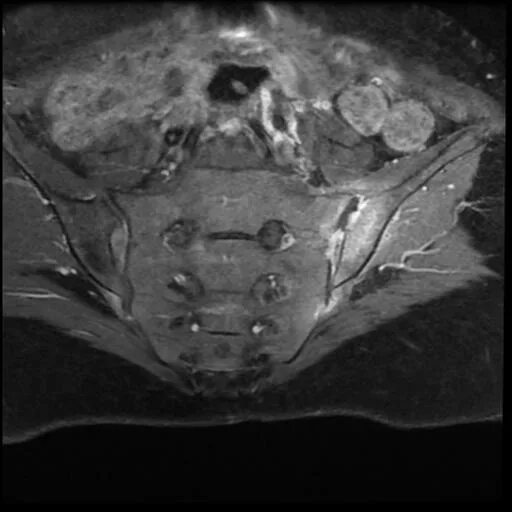

Сакроилеит на кт